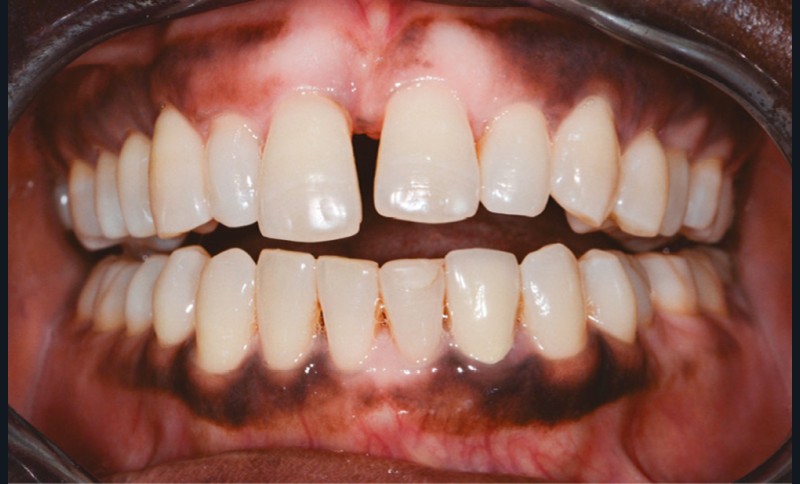

Une femme âgée de 33 ans, sans antécédents médico-chirurgicaux notables, consulte pour la correction de l’égression de son incisive centrale qu’elle juge disgracieuse dans le sourire (fig. 1).

L’observation clinique après traitement parodontal initial révèle, au niveau interarcade, des rapports de classe I molaire bilatéraux associés à des rapports de bout à bout incisif. Dans la dimension verticale, elle présente une légère infraclusion antérieure. On ne note pas d’anomalie de la dimension transversale (fig. 3 à 5). À l’examen intra-arcade, on constate des diastèmes maxillaires interincisifs (1 mm), en distal de 13 (0,5 mm) et de 24 (1 mm) ainsi que des malpositions unitaires (linguoversion de 12, rotation mésio-vestibulaire disto-linguale de 24). À la mandibule, on observe une couronne céramométallique au niveau de 32 plus large de 1,5 mm que les autres incisives ainsi qu’une rotation mésio- linguale de 35 (fig. 6 à 8). En diduction, on note une interférence au niveau de 24.